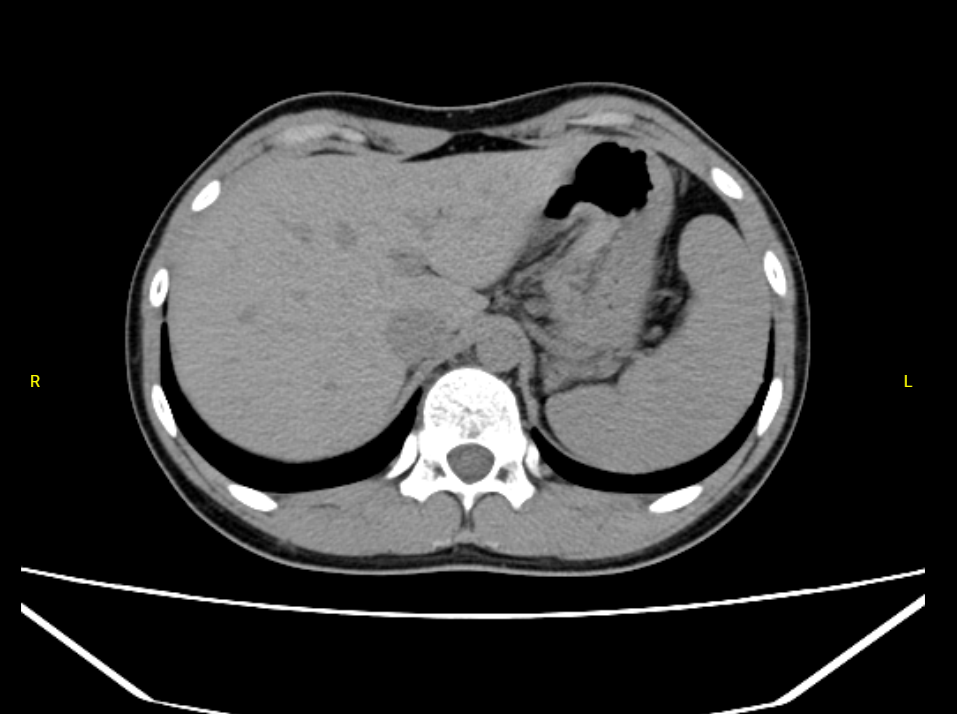

嘉利达医疗CT检查影像数据集

医疗CT检查影像数据集,包含匿名化的患者基础信息(性别、年龄区间、检查部位和检查报告)内容,可应用在医学影像分析、图像生成、图像去噪、图像分割等方面。如:1.医学影像分析:通过深度···

广州数据交易所